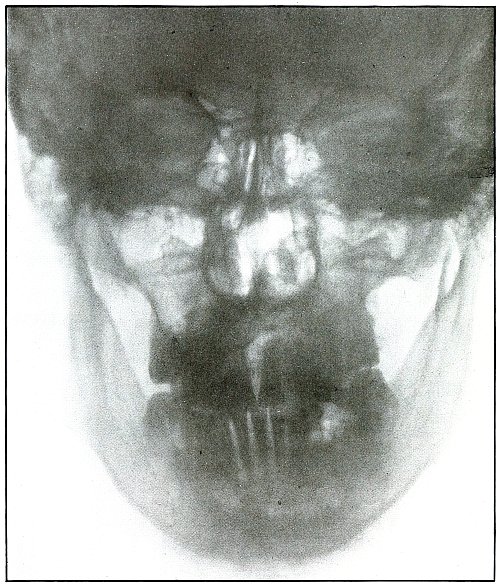

Plate 5.

_

Rifle—Plate 5.

HEAD.

Gunshot Fracture of the Body of Lower Jaw, with Great Fragmentation and Displacement.

Wound of entrance, to the left side of the median line of the lower jaw below the alveolar process, with course ranging downward and backward.

Wound of exit, with extensive laceration, beneath lower border of the bone.

The wound was caused by a rifle bullet at high velocity at or less than mid range. The fragments are many and rather small, so that much bone was lost through the wound of exit. This effect was produced by the splitting due to the relative friability of the bone and to the imparting of the momentum of the missile to the detached fragments, which, together with the missile, effected the considerable laceration of the wound of exit.

Treatment, difficult; guided by septic conditions and surgical means available.

Results in such cases are favorable to life but topically unsatisfactory. [Pg 22]